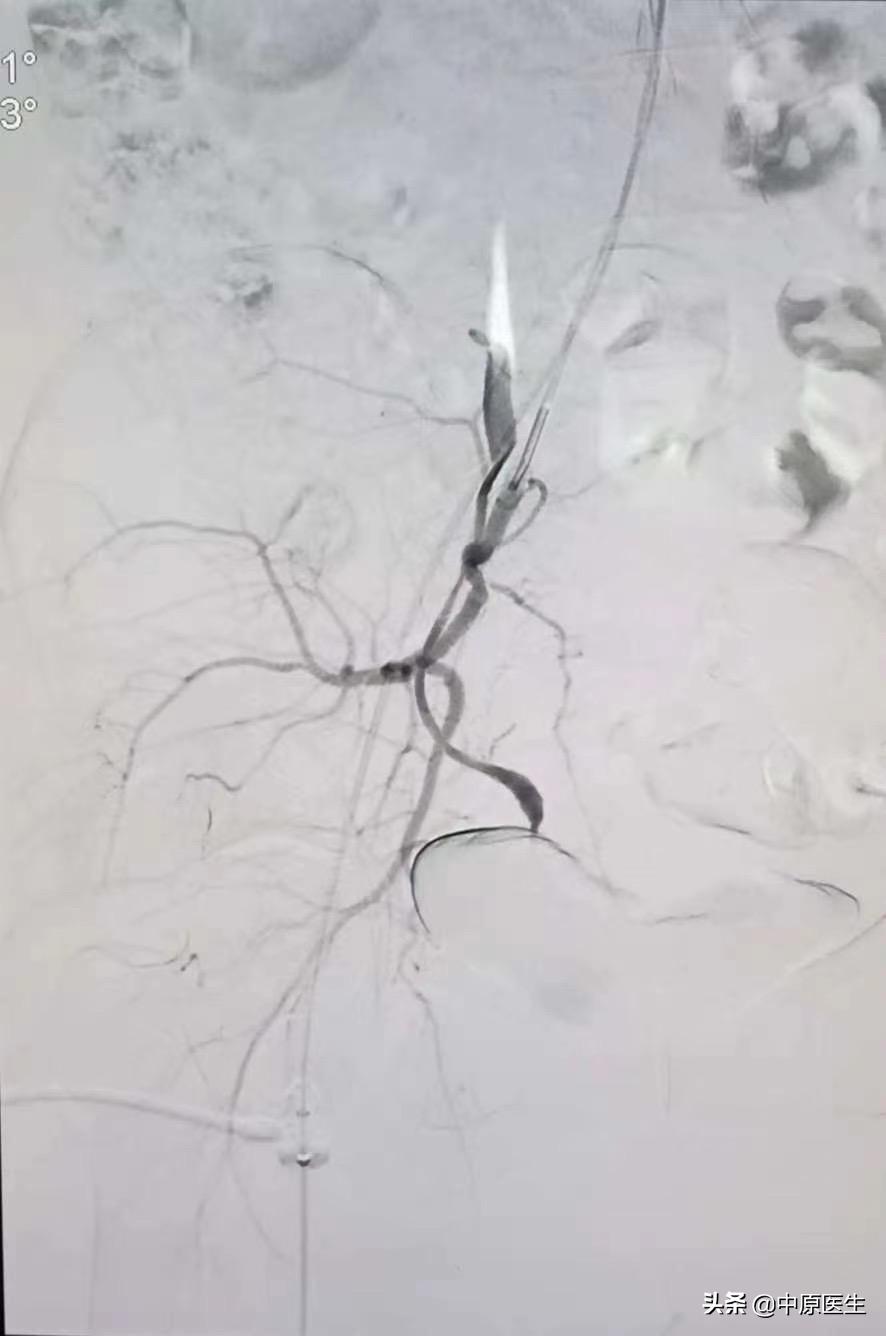

治疗计划制定后,我们立刻行动马,谁知一做血管造影才发现,怪哉!此女子非凡人也!两侧子宫动脉均不同于一般人,一侧是由卵巢动脉(锯齿状血管)长途奔袭去供应子宫血液,一侧是从阴部内动脉发出,两个血管发出角度都很刁钻,血管走形迂曲又比较细,做这样的血管介入类似于医学版“爬雪山过草地”,大家不禁倒吸了一口冷气!

难题摆在这,再难的骨头也得啃,再难的血管也得搞啊!谁让我们是医生呢!谁让患者的血管都不像教科书长得那样标准呢!跟自己鼓足劲,打打气,刘建文主任再次出发,见招拆招,小心翼翼,利用导管、导丝巧妙配合,更是他的耐心、细心、信心及过硬介入操作技术,战胜了种种不利因素,经过两个多小时的艰苦奋战,在有害射线的辐射下,浑身的衣服都湿透了,最后终于成功将两侧血管完美栓塞!利用自己的微创介入医学技术为妇产科医生手术保驾护航,为手术创造了安全的条件,终于保住了患者的子宫!尽管这样的手术太苦太累,当看到最后的手术图片,刘主任又露出了一贯的笑容,还不忘在综合介入微信群里跟大家做了一下交流和总结!